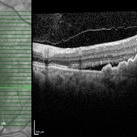

Polypoidal choroidal vasculopathy with cystoid macular edema

Nov 6 2022 by T. P . VIGNESH, MBBS,MS

SD-OCT of a 65 year old man revealing PCV with CME .

Photographer: Priyanka

Imaging device: Heidelberg Spectralis

Condition/keywords: polypoidal choroidal vasculopathy (PCV)